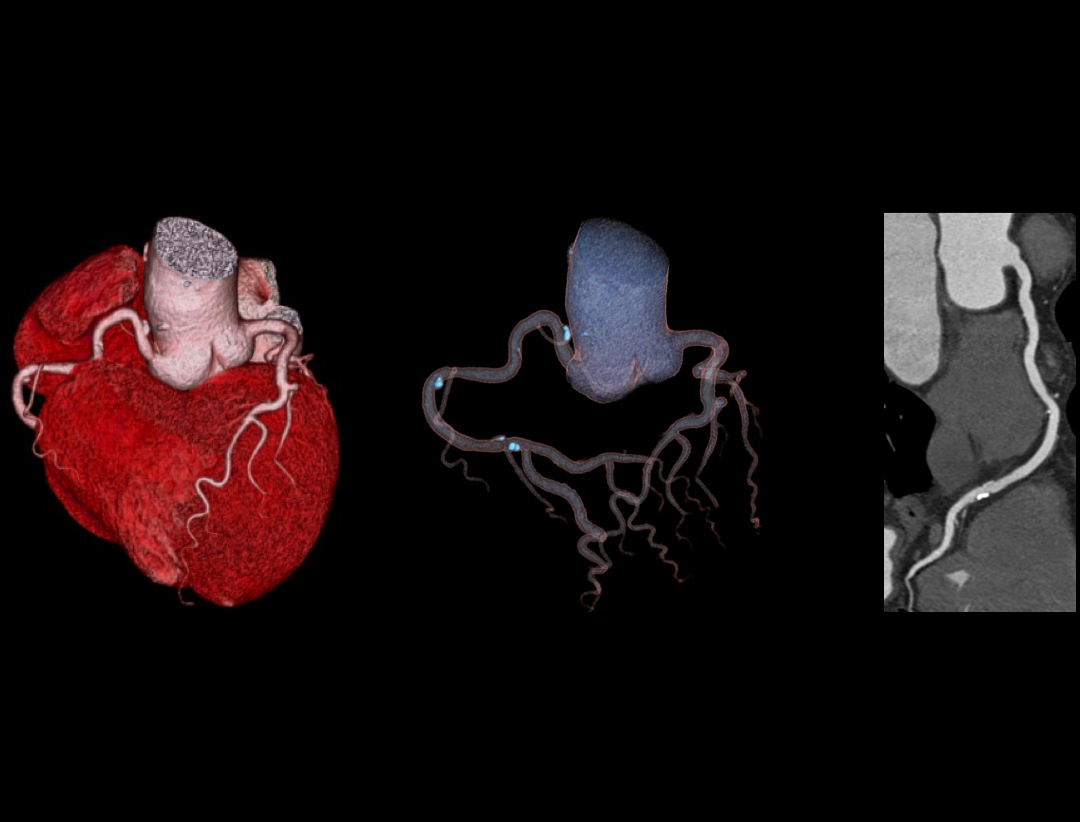

Excellence in Cardiac Imaging

CardioXphase

最適位相の自動選択。

100kW Max Generator Power

解剖学的構造を明瞭に描出。

0.3s Rotation Speed

時間分解能の向上。

Adaptive And Intuitive Applications

ワンクリック操作でより簡便な後処理の実現。

Clinical Application

High Heart Rate: 101 bpm

Mixed Coronary Atherosclerotic Plaque

Anomalous Origin Of Coronary Artery